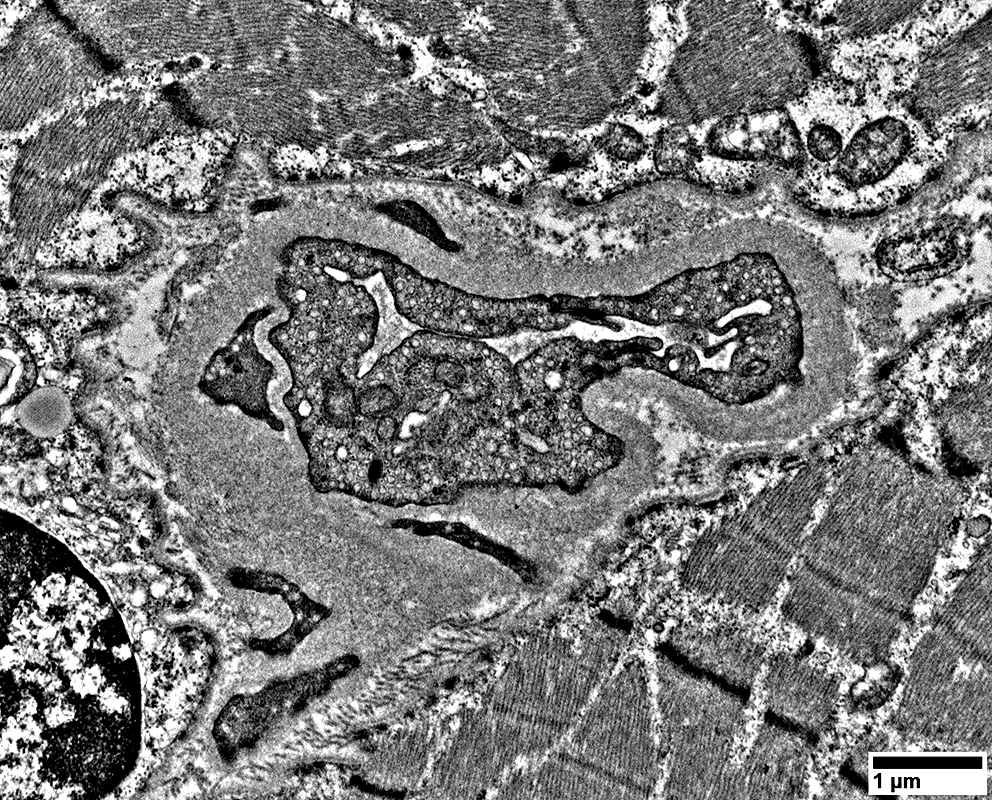

MELAS: Mitochondrial Ultrastructure

From: R Schmidt

Mitochondrial proliferation between sarcomeres

Mitochondrial proliferation & enlargement: Beneath muscle fiber surface